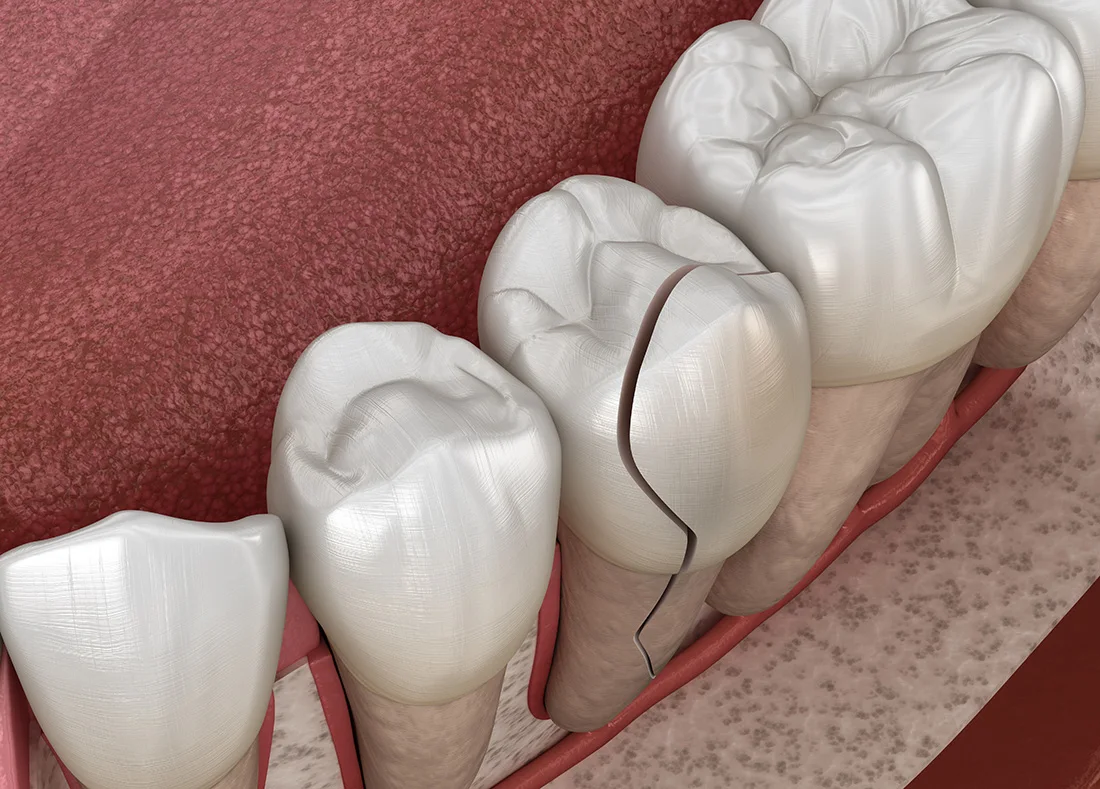

A toothache that lasts more than 1–2 days, especially if it’s throbbing, may be a sign of infection or an abscess. Try rinsing with warm salt water, applying a cold compress, and using OTC pain relief to stay comfortable. But remember, these are only temporary fixes. A dentist needs to assess the cause of the pain to provide long-term relief. Depending on the severity, we may recommend a root canal or other treatment to save the tooth and prevent the infection from spreading.

If your tooth has been knocked loose from trauma or an accident, you may still have a chance to save it—but you need to act fast. Refrain from wiggling or pressing on the tooth with your fingers or tongue, as this can worsen the injury. Call our office right away. If treated early, we can often stabilize the tooth with a splint and give it time to heal and reattach to surrounding bone and gum tissue. Waiting too long could lead to tooth loss, so don’t delay reaching out.